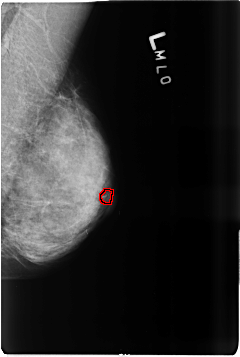

B_3516_1.LEFT_MLO

LEFT_MLO LINES 4632 PIXELS_PER_LINE 3112 BITS_PER_PIXEL 12 RESOLUTION 50 OVERLAY

FILE: B_3516_1.LEFT_MLO.OVERLAY

TOTAL_ABNORMALITIES 1

ABNORMALITY 1

LESION_TYPE CALCIFICATION TYPE PLEOMORPHIC DISTRIBUTION CLUSTERED

ASSESSMENT 4

SUBTLETY 3

PATHOLOGY MALIGNANT

TOTAL_OUTLINES 1

BOUNDARY